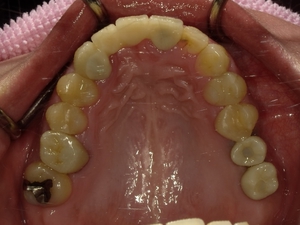

30代女性非抜歯

BEFORE→AFTER

〇ご相談内容:歯の叢生(ガタガタ)

〇矯正の種類:マウスピース型矯正「インビザラインGo」

〇治療期間:16週間

〇治療費用:44万円(税込)